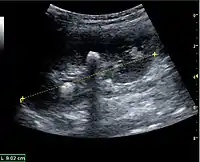

Benign solid tumors of the kidney are oncocytoma and angiomyofibroma. Oncocytoma has a varying ultrasonic appearance, but may have a central scar or calcification as a hallmark. Angiomyofibroma are often found in patients with tuberous sclerosis. They are composed of fat, smooth muscle tissue and vascular elements. The echogenicity is governed by the composition of these elements, but the lesion is often hyperechoic (Figure 11 and Figure 12).[1]

Figure 11. Angiomyolipoma seen as a hyperechoic mass in the upper pole of an adult kidney.[1]